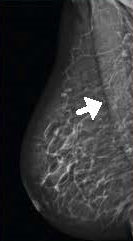

Planmed Clarity™3D – цифровая система для маммографии с томосинтезом. Метод томосинтеза позволяет более четко визуализировать уплотнения и аномальные изменения молочных желёз, что увеличивает шанс на выявление рака груди на ранних стадиях.

- ContinuousSync -and-Shoot™ - синхронизированная съёмка для непрерывной визуализации, которая позволяет получать чёткие снимки без расплывчатых границ. Синхронизацию обеспечивает детектор, который всегда сфокусирован на фокальном пятне, в то время как топографическая трубка движется по заданным параметрам. Такая технология позволяет увидеть мельчайшие детали тонких тканей и микроскопических кальцификаций.

- TomoMarker™ - это чёткие снимки без артефактов с увеличенной резкостью. Специалист видит больше, чем ранее было возможно, за счёт оптимальной геометрии съёмки под углами +/- 15°. Технология проводит итоговую итеративную реконструкцию, предоставляя качественную и чёткую картинку.